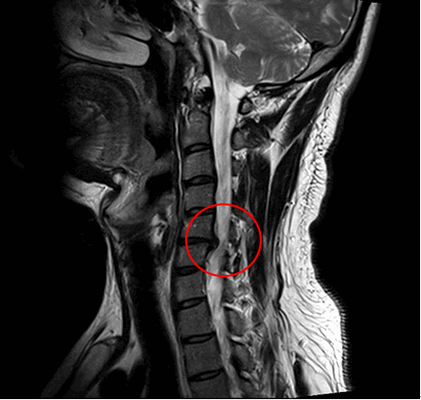

Ущемление позвоночного канала вледствие выпячивания диска.

- МРТ позвоночника. Определяется снижение интенсивности сигнала на Т1-взвешенных снимках и его повышение на Т2-взвешенных изображениях, деформация межпозвоночных дисков, структурные изменения тел позвонков. Чувствительность магнитно-резонансной томографии достигает 96%, точность - 94%, поэтому ее считают «золотым стандартом» диагностики.